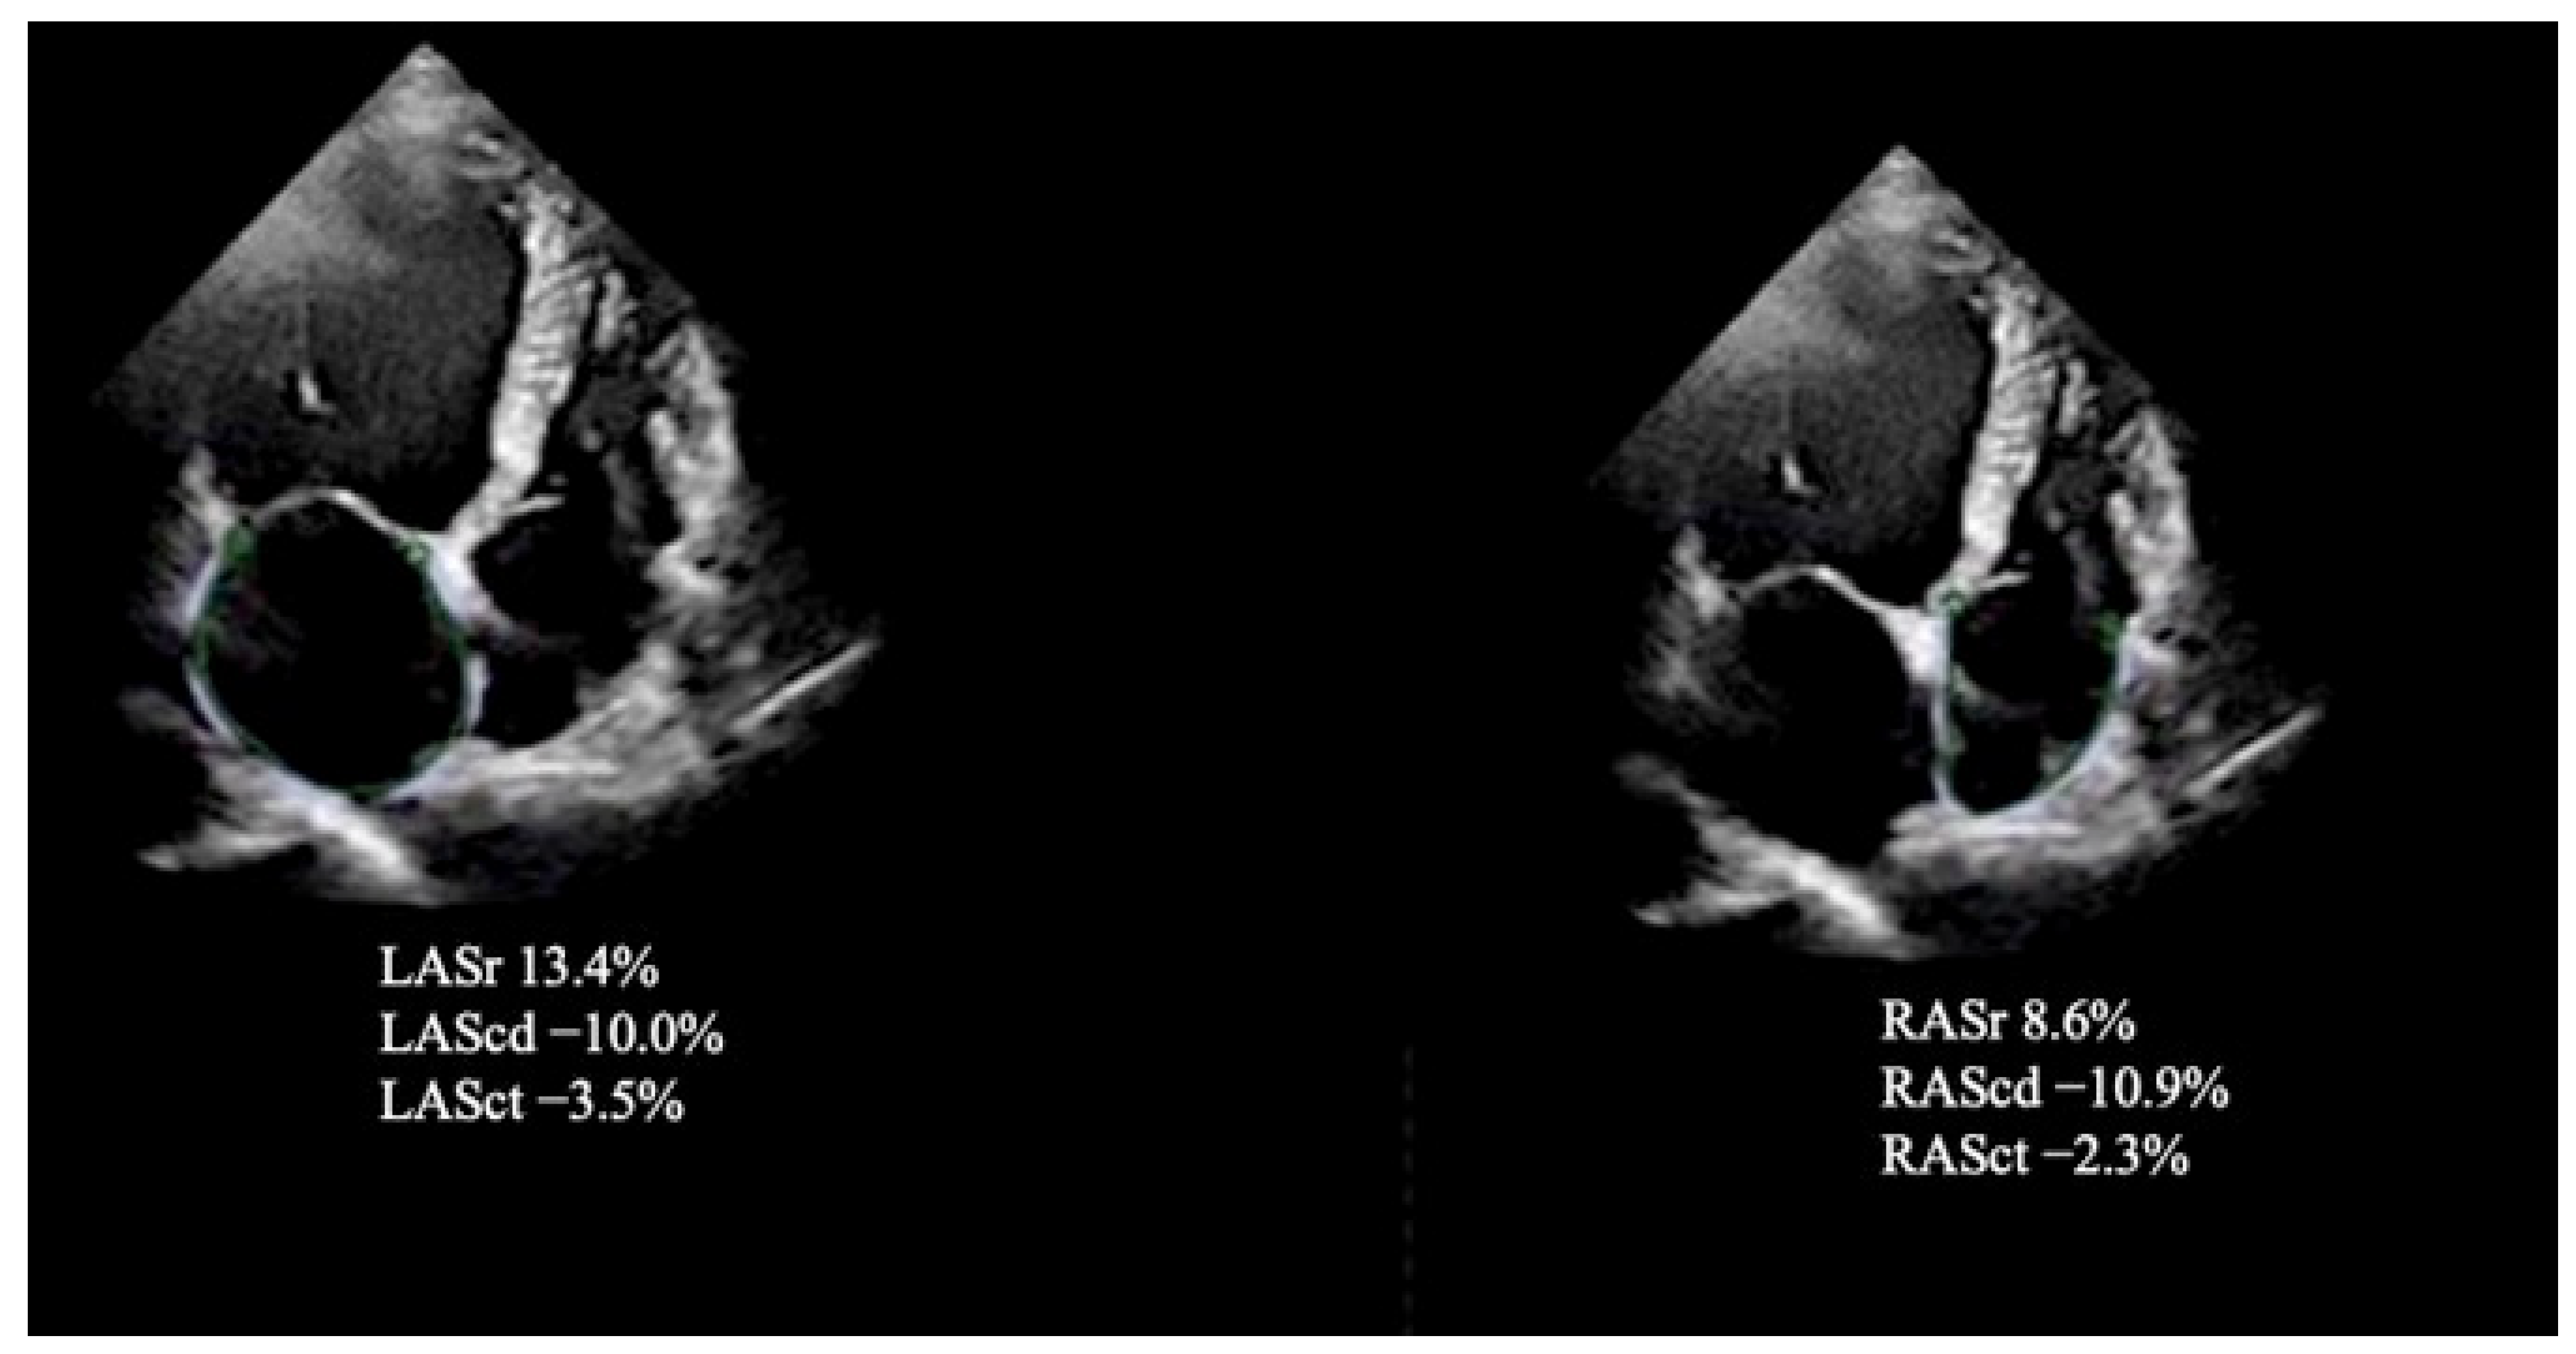

| RAScd, % | −13.5 ± 5.1 | −18.0 ± 4.8 | <0.001 |

| RASr, % | 26.9 ± 6.4 | 31.6 ± 5.1 | <0.001 |

| RASct, % | −10.4 ± 6.9 | −14.6 ± 3.1 | <0.001 |